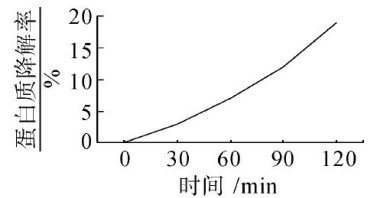

研究报告专论 | 多聚谷氨酸水凝胶特性分析与溃疡性结肠炎治疗效果评价

研究报告专论 | 多聚谷氨酸水凝胶特性分析与溃疡性结肠炎治疗效果评价